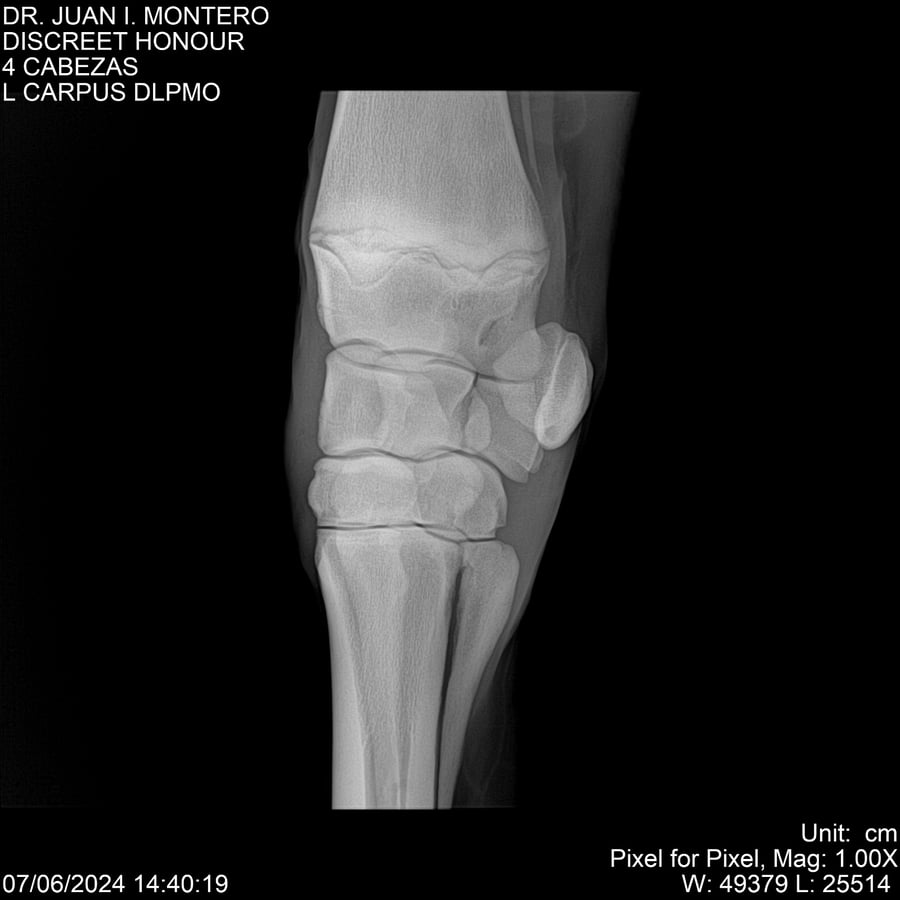

LOTE 6, DISCREET HONOUR 🔥 🔥 🔥 Lote Anterior Volver al remate Lote Siguiente Ficha Contacto Montevideo - Ficha del Lote Identificador: #281093 Categoría: Yeguarizos Montevideo - 82 Visualizaciones ClicData Contacto Empresa: Abelenda N. R., Walter Hugo Nombre*: Teléfono* : E-mail* : Mensaje Enviar Registrese gratis Este contenido Exclusivo está disponible sólo para usuarios registrados Ingresar